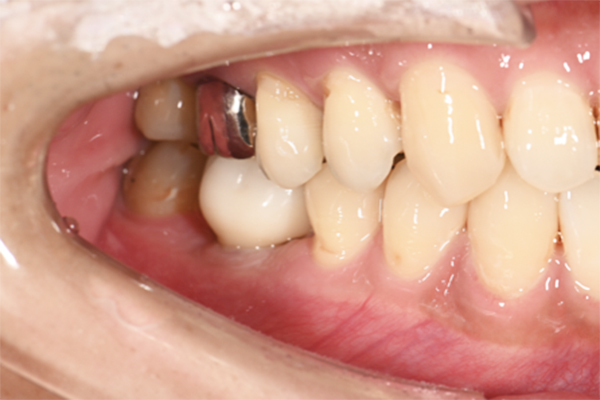

| 主訴 | 奥歯で噛めない、顎が痛い |

|---|---|

| 治療内容 | 奥歯のインプラント治療、前歯・奥歯の被せ物治療 |

| 治療期間 | 6ヶ月 |

| 治療費 | 350万円 |

| 治療リスク | 被せ物をつけた初期の段階で歯がしみることがある(時間とともに改善する) インプラント治療後に3日程度痛みと腫れを伴うことがある |